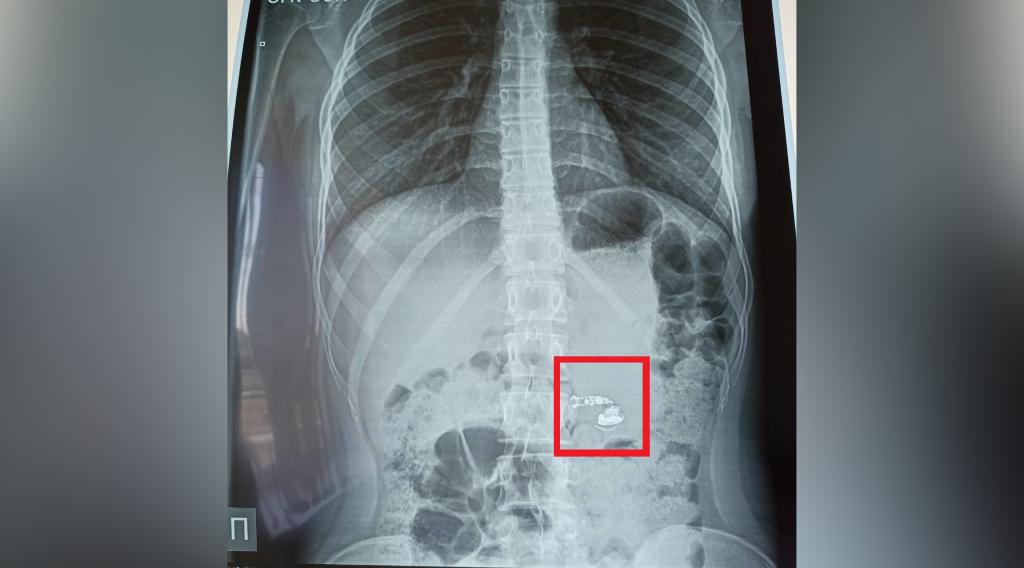

В одну из уфимских больниц поступила 15-летняя пациентка, проглотившая во сне беспроводной наушник. Об этом рассказал глава Минздрава республики Айрат Рахматуллин. Девочка проснулась посреди ночи от боли в горле, на место выехала бригада скорой, которая госпитализировала пострадавшую. В больнице рентген показал, что наушник оказался в кишечнике

«Девушку госпитализировали в отделение детской хирургии. В этом случае все обошлось без оперативного вмешательства. Предмет вышел из организма естественным путем, без осложнений», — рассказал Рахматуллин. Теги: